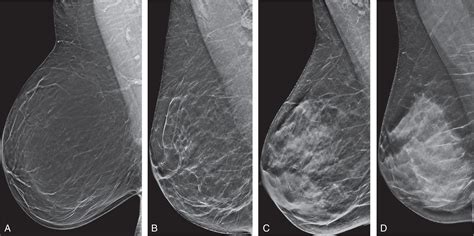

Understand your Bi Rads 3 breast imaging results with our expert guide. We explain what this classification means for your health, the typical follow-up imaging requirements, and the low risk of malignancy. Learn why a short-term breast cancer screening interval is recommended and how radiologists manage these probably benign findings to provide you with peace of mind.